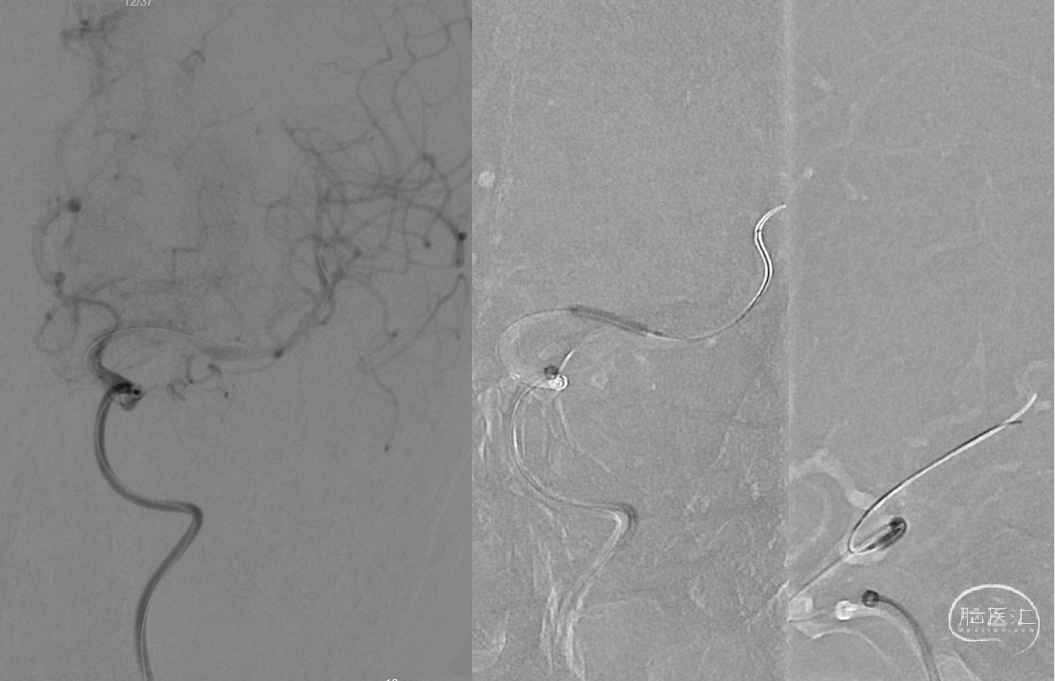

ASAHI微导丝携带Navien-72及SL-10微导管,造影血管通畅,前向血流缓慢,给予Gateway 2.0mm×15mm球囊球扩

观察血管有所回弹,给予Gateway球囊以6ATM压力缓慢扩张,并缓慢注射替罗非班5ml

Neuroform Atlas 4.0mm×21mm支架释放满意

术后左颈内正侧位

以泥鳅导丝携带8F Guiding及多功能造影管路图下同轴到颈内动脉,撤出多功能管。ASAHI-0.014in×200cm微导丝携带Navien-72及SL-10微导管到达颈内动脉末端,微导管造影再次证实大脑前动脉通畅,左侧大脑中动脉M1闭塞,微导丝通过闭塞段顺利证实为真腔,中间导管造影提示远端血流存在,前向血流缓慢,M1处重度狭窄,交换Transed 0.014in×300cm微导丝,经微导丝上Gateway 2.0mm×15mm球囊,与M1狭窄处行6ATM缓慢扩张,观察前向血流有所好转,于微导管处行替罗非班5ml缓慢注射接触性溶栓,观察5分钟,血管有所回弹。

再次给予Gateway球囊以6ATM压力缓慢扩张,并缓慢注射替罗非班5ml,观察20分钟,M1处血管毛糙,血管回弹明显,给予经微导管释放Neuroform Atlas 4.0mm×21mm支架满意。复查造影左侧大脑中动脉及大脑前动脉显影良好,mTICI3级,观察10分钟后,再次复查造影左侧大脑中动脉及大脑前动脉显影良好。行Dyna CT见未见明显出血灶。